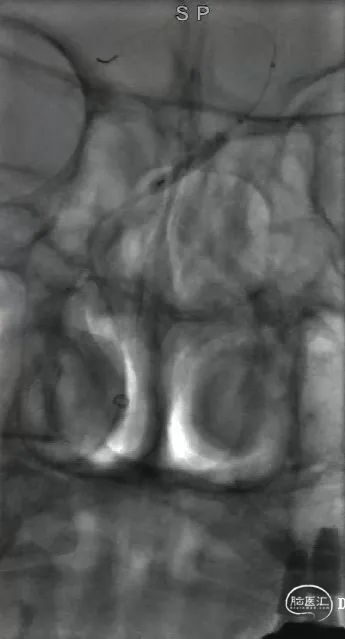

椎动脉造影显示基底动脉起始部以远未显影。

造影

基底动脉中下段局限性狭窄,远端血管显影良好,替罗非班推7,走6,并观察半小时。

再次复查造影,血管情况大致同前,结束手术。